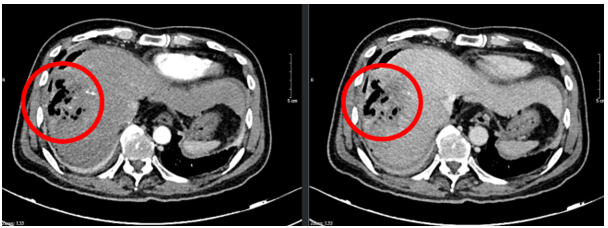

- Chụp cắt lớp vi tính ổ bụng:

Hình 1: Hình ảnh chụp cắt lớp vi tính ổ bụng: Nhu mô hạ phân thùy S7-8 có khối (vòng tròn đỏ) tỷ trọng hỗn hợp kích thước 81x51mm gồm phần tăng tỷ trọng của vật liệu can thiệp và nhiều bóng khí tạo thành ổ tụ khí trong nhu mô kèm phần hoại tử dạng dịch, không có huyết khối.